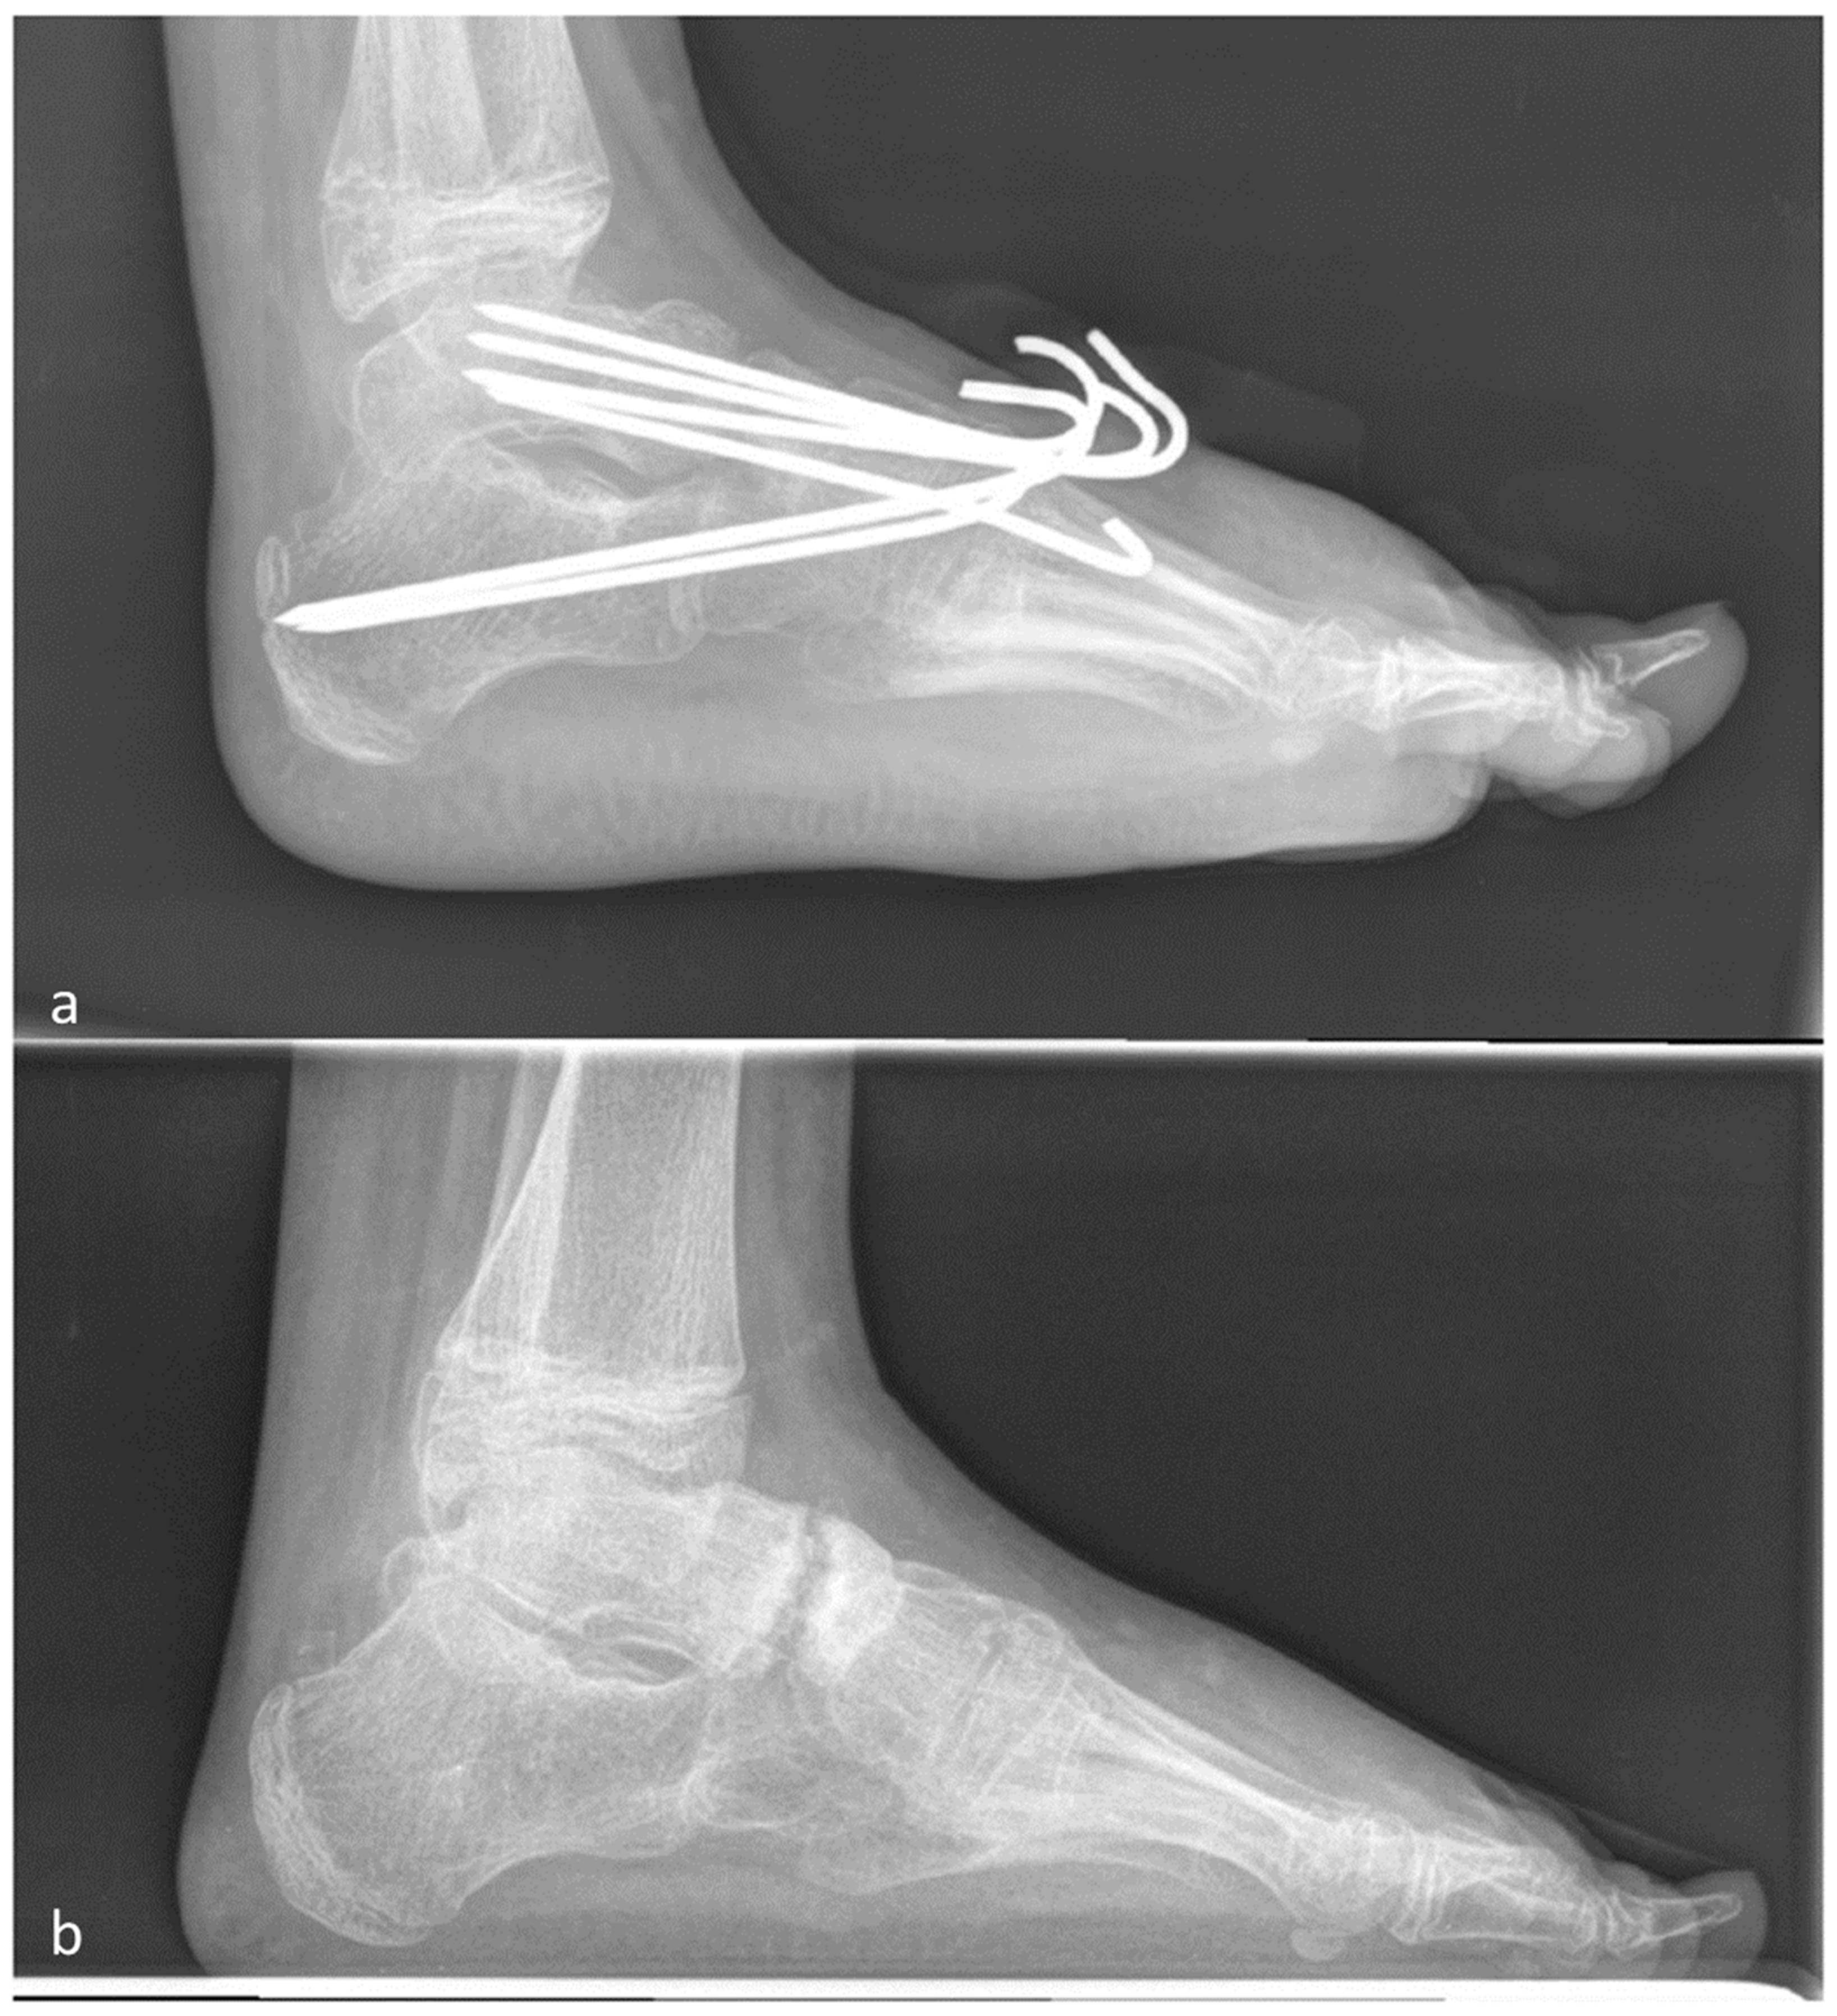

2.1. Operative Procedure

2.2. Clubfoot

2.3. Pes Cavovarus

2.4. Pes Planovalgus

2.4.4. Triple Fusion